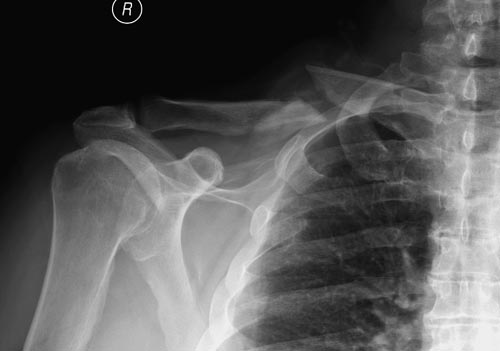

В данном случае надо подождать, случай не ургентный! Тем более, у большинства со старым ложным суставом функцию конечности не теряется, и они бессимптомны. Боли бывают только в начальном периоде, затем интенсивность уменьшается, и к ним привыкают. К врачам они обращаются, когда имеется косметический дефект, или когда им напоминают о ложном суставе.

В заключение, только 25% изолированных переломов ключицы, леченных консервативным методом не срастаются, а из них 1/3 симптоматические. Болезненные ложные суставы надо оперировать, и здесь представлен случай свежего болезненного ложного сустава, оперированного через 4 месяца.